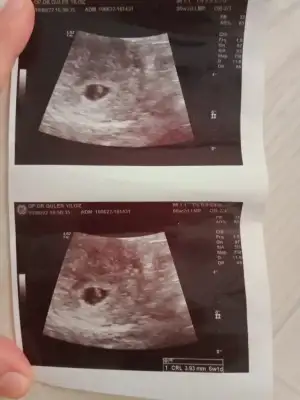

prenses gibiMerhaba benimkinide bakabilirmisiniz 3.hamileleik 7.0 hafta karından

sanki prenses gibiMerhabaPasha22 bana da yorum yapabilir misin biri 6+1 diğeri 8+1 karından